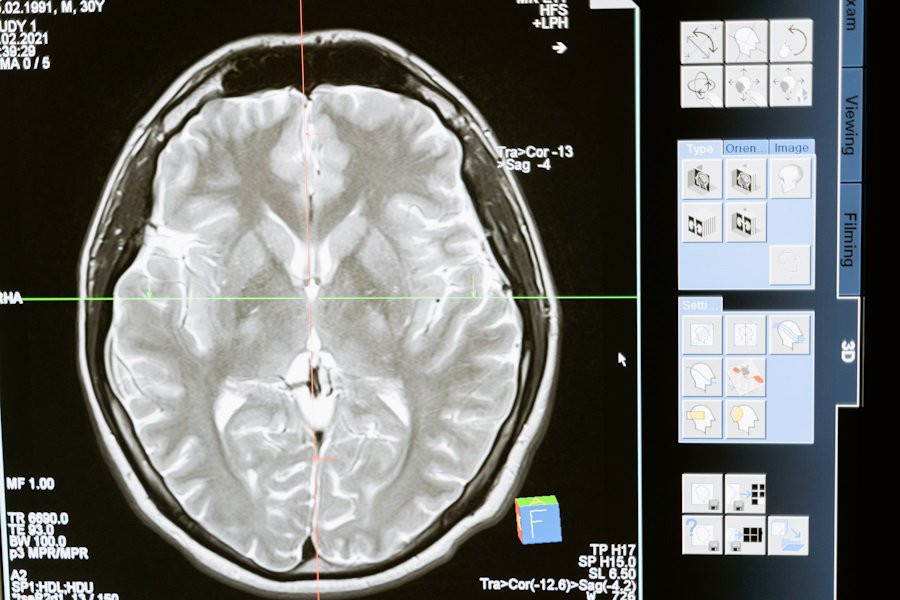

В новой статье, опубликованной в журнале Lancet Neurology, нейробиологи из Western University, Lawson Health Research Institute и Harvard University представляют прорывные разработки в области нейровизуализации, которые могут раскрывать мысли, действия и намерения пациентов с травмами мозга, основываясь на паттерне активности в их мозге. Это открытие может существенно улучшить прогнозирование выживаемости пациентов в отделениях интенсивной терапии (ОИТ).

Учёные объединили методы нейровизуализации, включая функциональную магнитно-резонансную томографию (фМРТ), электроэнцефалографию (ЭЭГ) и функциональную спектроскопию в ближнем инфракрасном диапазоне (фНИРС), для оценки состояния пациентов в первые дни после травмы.